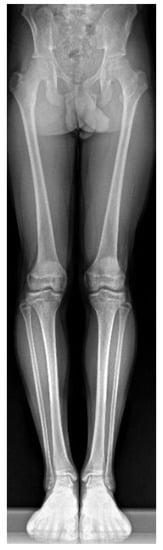

A histological examination proved that the lesion was indeed an osteoid osteoma. Further checkups have already been carried out at 3 months and at 6 months post-op. The patient has returned to his regular sports routine, and the musculature on his right lower extremity is gradually regenerating (Figure 8). At the 6-month post-op check-up, we took a long-format standing radiograph, which showed a slight valgus orientation of the proximal femurs; however, the stability of the right hip joint was not jeopardized even after our procedure (Figure 9). An MRI scan was also taken, and it proved the complete removal of the OO as well as the healing of the working canal (Figure 10). A further check-up is planned at one-year post-op.

Figure 9.

Long-format X-ray of the lower limbs showing a slight bilateral acetabular dysplasia of the hips due to a history of DDH (Developmental dysplasia of the hips). The centrum–collum–diaphysis angles are 132° on the right side and 134° on the left side.